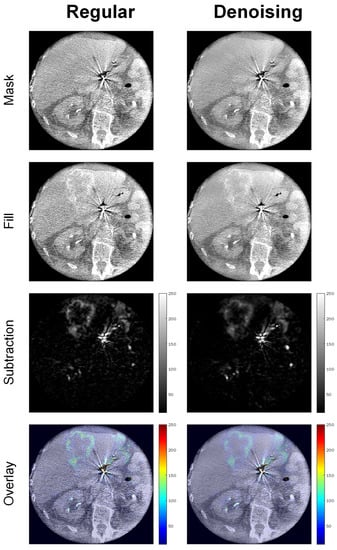

Figure 7 shows example images of a 68-year-old adipose male patient (BMI = 30) undergoing SIRT for hepatic uveal melanoma metastases, illustrating significantly enhanced image quality by noise reduction and preserved localizability of the interventional target in the intensity overlay map.

Figure 7. Example images of a 68-year-old adipose male patient (BMI = 30) undergoing SIRT for hepatic uveal melanoma metastases.